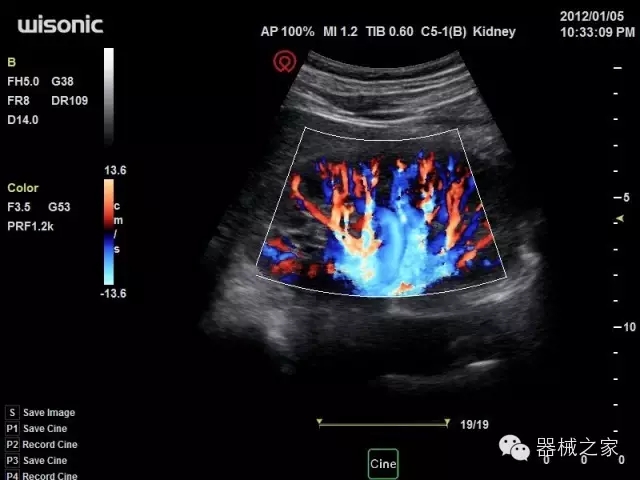

經(jīng)典產(chǎn)品:四葉草

臨床圖片賞析

產(chǎn)品特點(diǎn)

·全球目前唯一一款配備主機(jī)雙探頭接口,整機(jī)重量(含電池)在5公斤以內(nèi)的便攜式彩超;

·獨(dú)有的HoloTM PW 實(shí)時(shí)3取樣門PW成像技術(shù),精確進(jìn)行血管診斷;

·一鍵優(yōu)化B、Color、PW,Auto Doppler自動(dòng)識(shí)別血管位置、偏轉(zhuǎn)角度等,提高工作效率;

·30°超廣角精細(xì)偏轉(zhuǎn)成像技術(shù),更優(yōu)異的頻譜圖像;